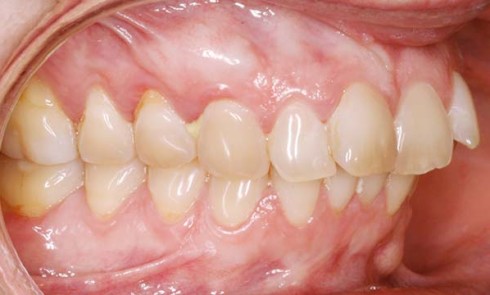

PrésentationLa patiente âgée de 21 ans présente une classe I dentaire bilatérale associée à une bi-proalvéolie sévère et à une...

PrésentationLa patiente âgée de 40 ans présente une classe II bilatérale associée à une dysharmonie dento-maxillaire modérée et à une...